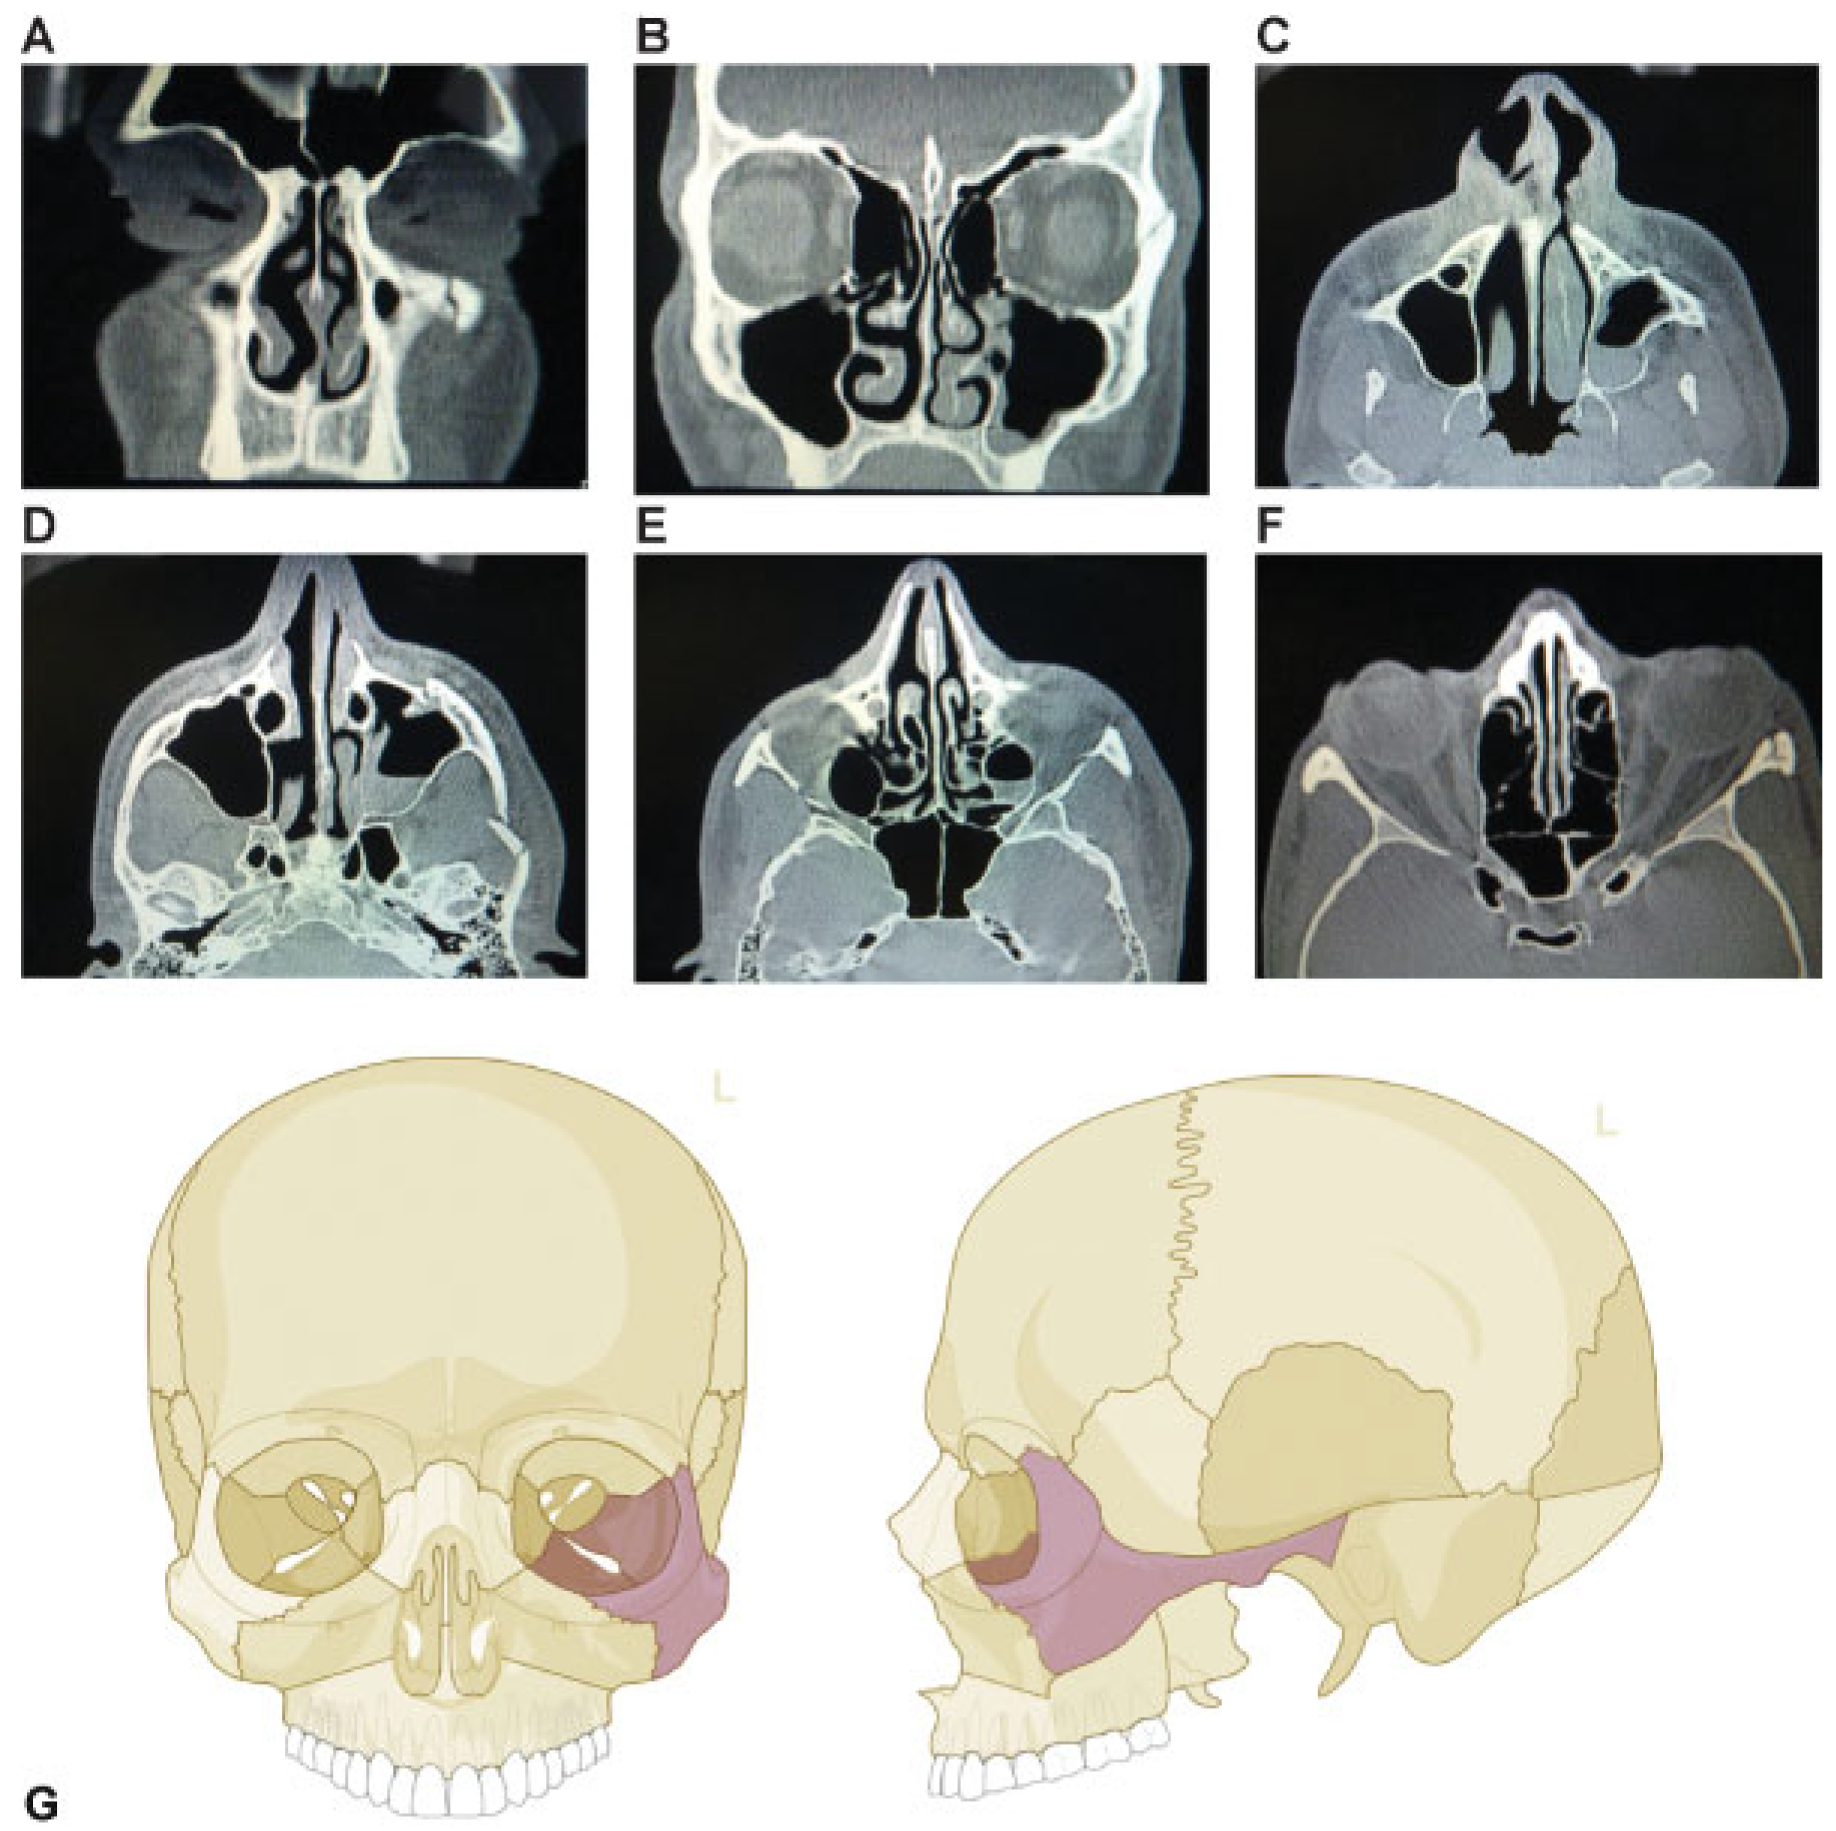

This coding system allows description of most relevant fracture patterns as illustrated in the case examples, such as LF fracture patterns as well as the differentiation between unilateral or bilateral fracture patterns. In a series of three case examples, we illustrate the coding of a fracture of the upper central midface (Figure 5); a bilateral LF I (LCM), LF II (ICM), nasal bone fractures (UCM), and a zygoma fracture on the left side (Figure 6); a zygoma fracture with lateral orbital wall involvement (Figure 7); and a fracture of the origin of the zygomatic arch (Figure 4). A range of additional fracture patterns are presented in a special case appendix [7] as electronic supplement to this issue of the Journal at www. aocmf.org/classification.

Figure 5. Fracture of the upper central midface. Imaging: CT scan axial view (A–D) and coronal view (E, F). Description: Nasoorbitoethmoidal (NOE) fracture with involvement of nasal bones bilaterally (UCM), medial orbital and inferior orbital rim left side (UCM and ICM), the anterior medial wall (Om) and the orbital floor (Oi) are fractured. (G) Level 2 Code: 92 U.Omi.Ii. This case example CMTR-92-001 is made available electronically for viewing using the AOCOIAC software at www.aocmf.org/classification.